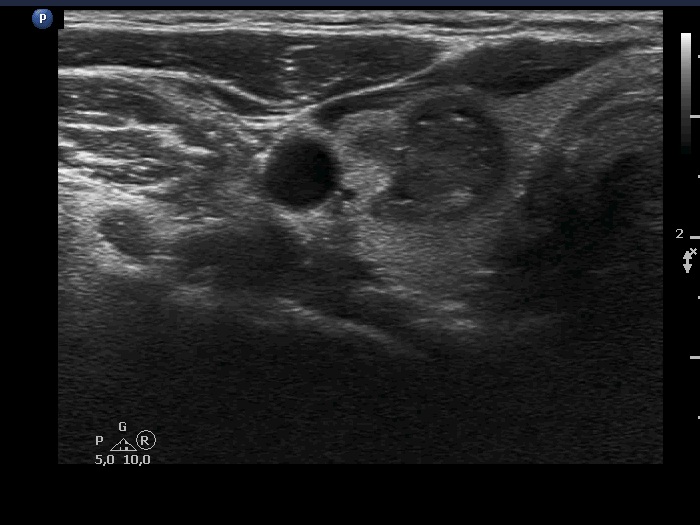

Ultrasonography. The thyroid was echonormal and had multiple moderately hypoechoic and hyperechoic nodules which showed various degrees of cystic degeneration. The largest nodule in the right lobe was dominantly cystic and presented with minimally hypoechoic solid part which included hyperechoic figures. The largest nodule in the left lobe had irregular margins.

The right nodule presented with a patchy echonormal area having punctate echogenic foci, a pattern resembling amyloid deposit.

The left nodule had irregular borders.